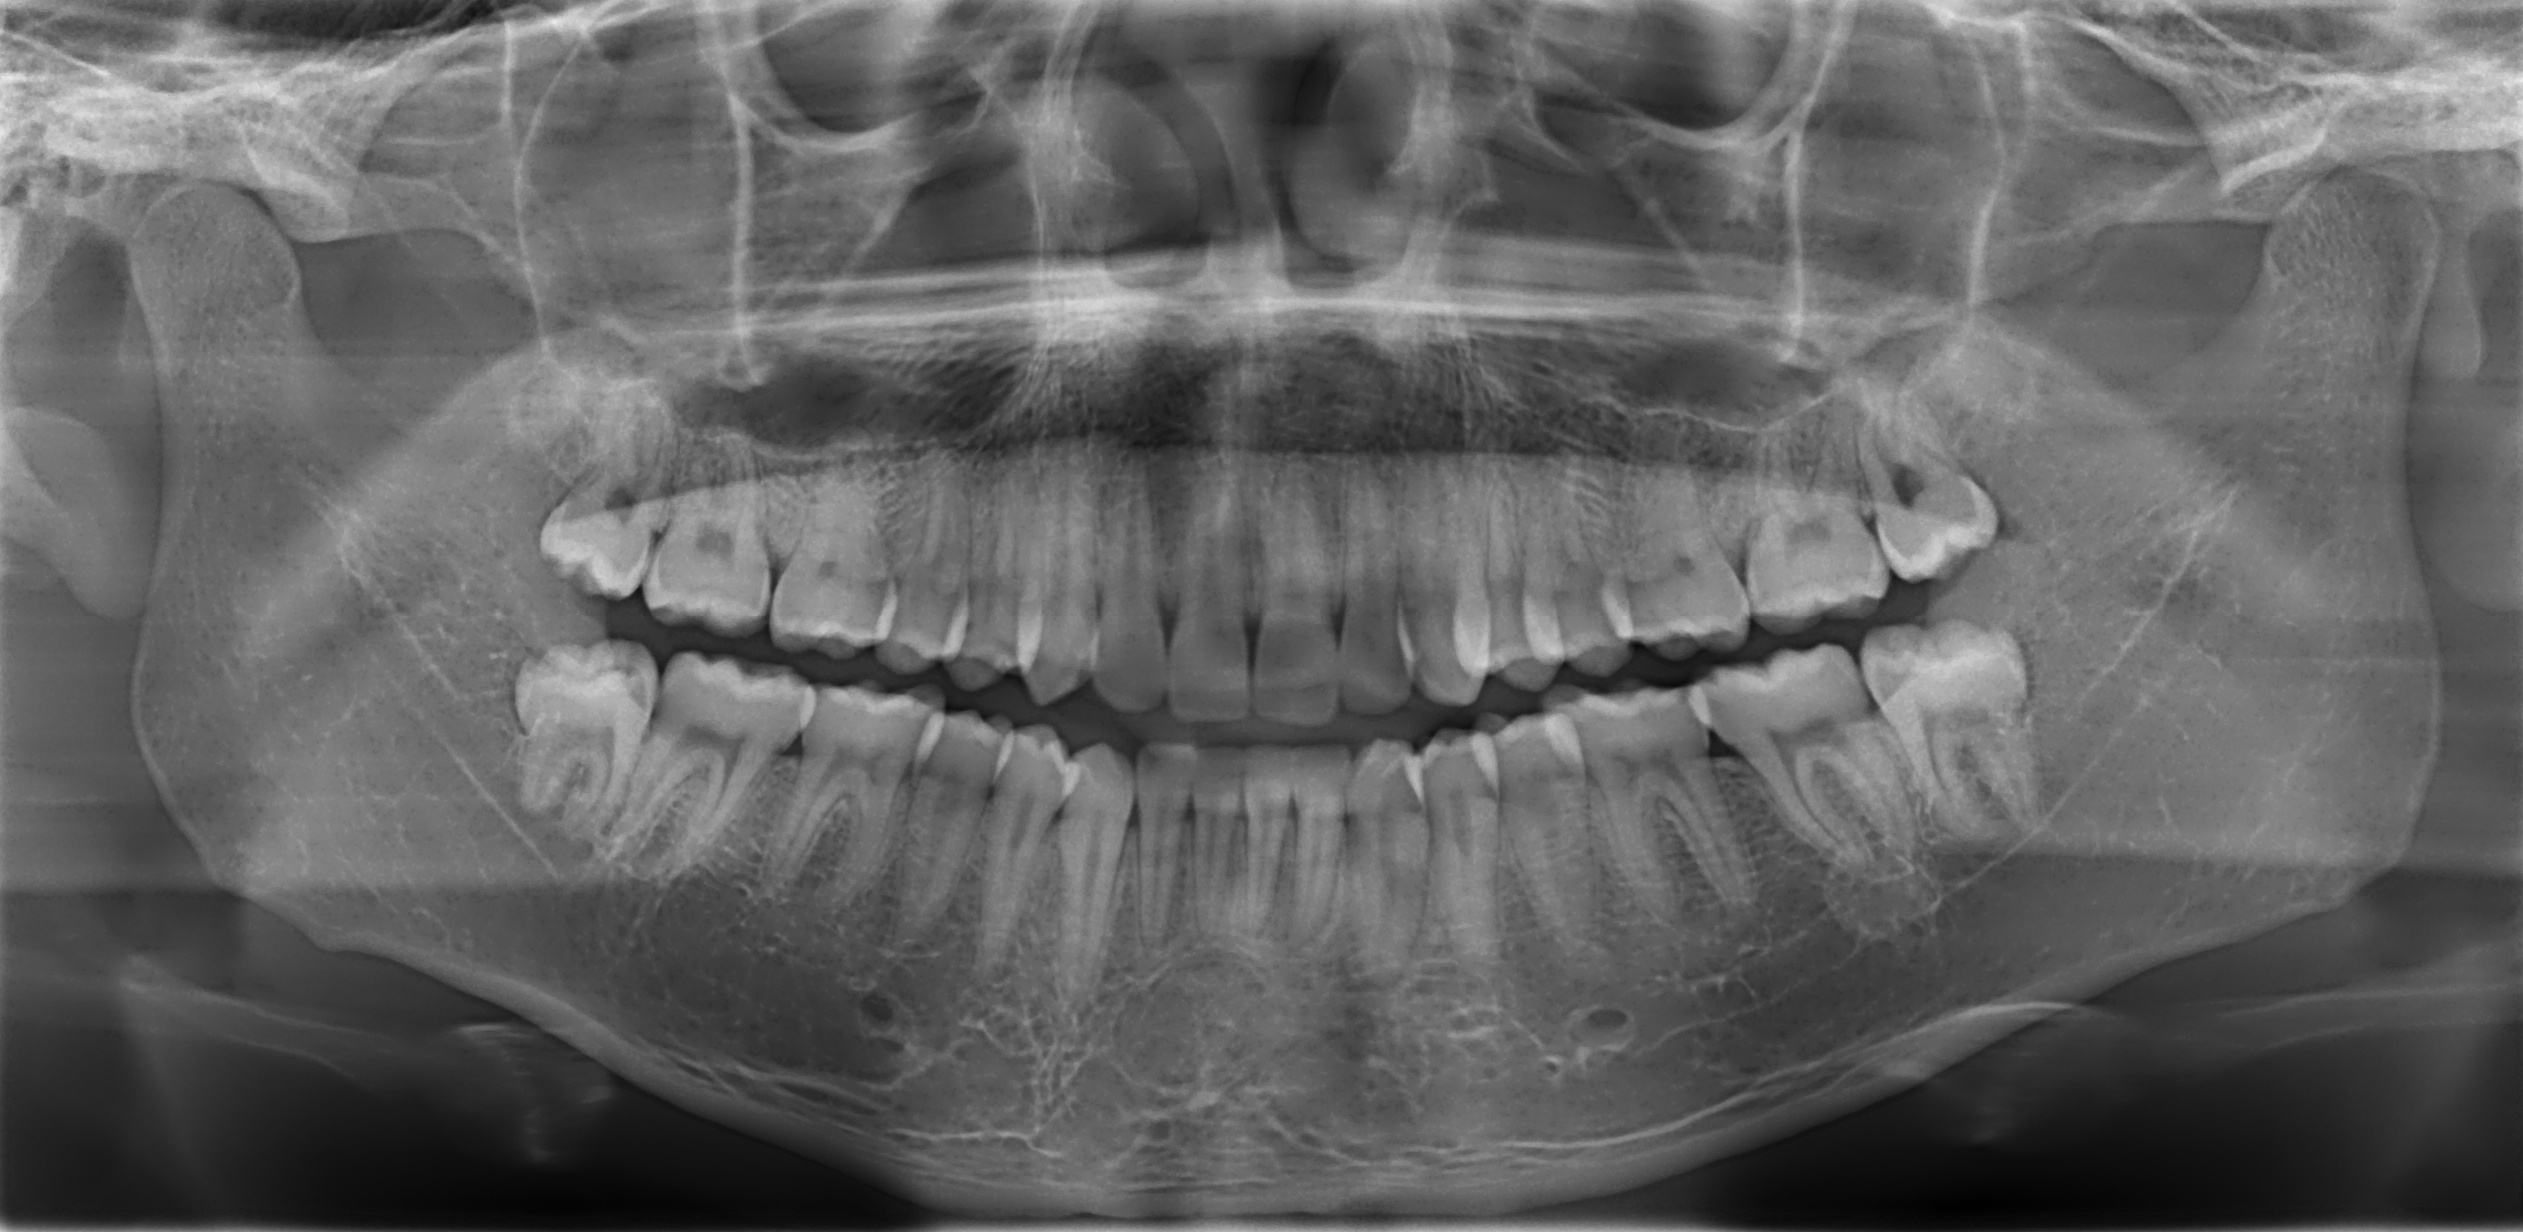

This is an example of an image used to train our model. The model has been trained with data from 12 countries and 4 continents so it can generalize to data from never seen samples. It gets a mean absolute error of 1.07 years and an accuracy of 88.38% (for the 18 years threshold) in test. Regarding never seen samples, it gets a mean absolute error of 1.21, 1.45, 1.36 and 1.51 years and an accuracy of 92.04, 81.97, 85.03 and 86.08% in four samples from Russia, Ethiopia, Egypt and Australia, respectively.